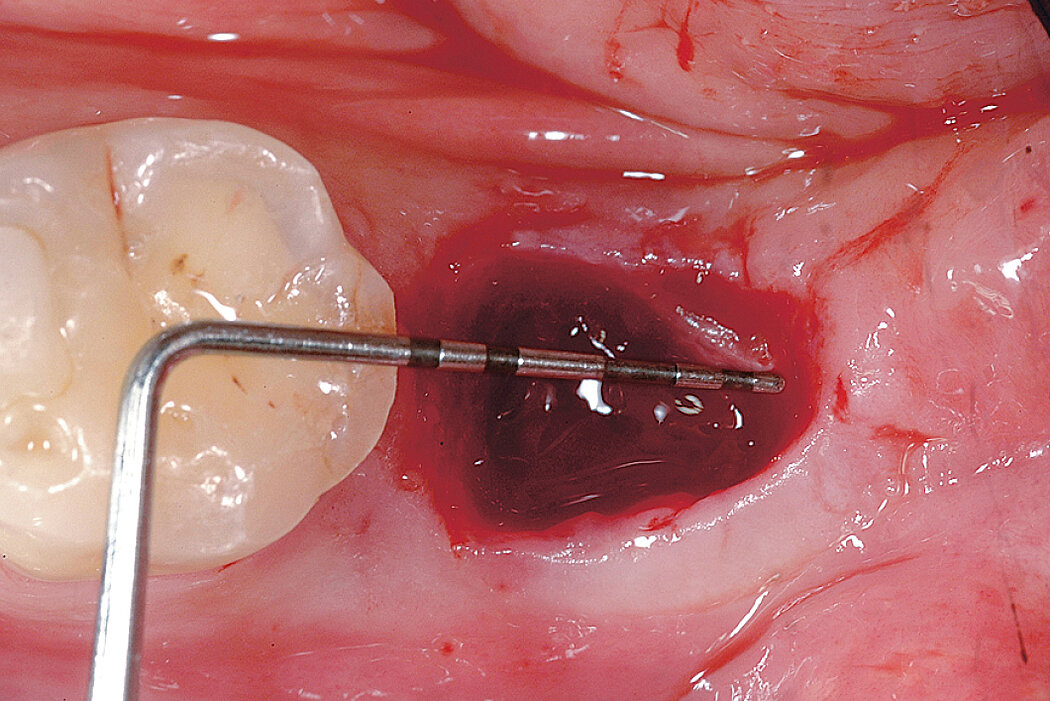

Delayed implant placement with a thin and defective buccal bone wall (open-healing approach)

Clinical challenge

Geistlich Bio-Gide® Shape is a really user-friendly product that can easily be used in the management of postextraction sites for ridge preservation.

Aim / Approach

Delayed implant placement to restore tooth 34. Minimally invasive procedure without mobilization of the flap to cover the graft: healing by secondary intention (open healing).

Conclusion

Geistlich Bio-Gide® Shape in combination with Geistlich Bio-Oss® Collagen preserved largely the ridge dimensions after tooth extraction. Implant can be placed without need of a second bone grafting at time of implant placement.